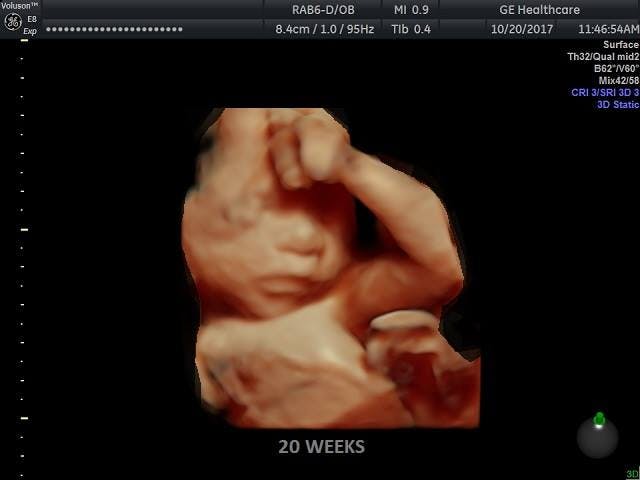

Screenshots taken straight from the report list out the prices of various body parts and organs. In the first image below, Advanced Bioscience Resources (ABR) paid $240 to Planned Parenthood of the Pacific Southwest for “four fetuses,” then turned around and charged $6,825 for twenty “specimens” from those aborted babies. At least one of these babies was 20 weeks old.

Famous Nilsson photo of preborn baby at 20 weeks (Photo credit)